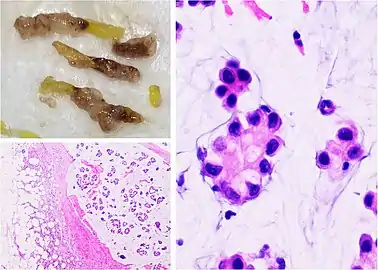

Mucinous carcinoma of the breast: Gross pathology (upper left) of mucinous carcinoma shows gelatinous areas. Histopathology shows clusters or nests of tumor cells floating in pools of extracellular mucin.[3]

Mucinous carcinoma of the breast: Gross pathology (upper left) of mucinous carcinoma shows gelatinous areas. Histopathology shows clusters or nests of tumor cells floating in pools of extracellular mucin.[3]